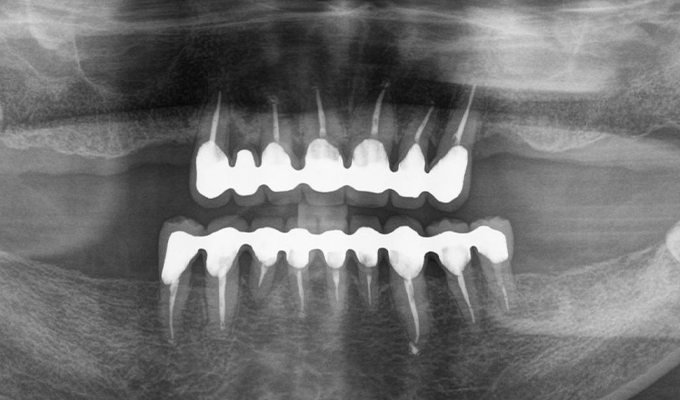

case1インプラントとメタルボンドブリッジの症例

初診時(2010年)

- 初診時の年齢

- 60代女性(2010年)

- 主訴

- ちゃんと咬めるようになりたい。最近孫が生まれたから一緒に歌ったりしたいけど、今は歌うこともできないから・・・・。と

- 治療内容

- 5年ほど前に入れ歯を作ったそうですが合わなかったので使用してなかったせいか前歯がグラグラになっていて今にも抜けそうな状態でした。

保存が難しい歯を抜歯し、上はインプラント8本、下は奥歯にインプラント4本埋入しました。

補綴は変色しないメタルボンドを選択されたので治療完了して11年経過してもとてもきれいな状態で維持されています。

初診時にお話しされていたお孫さんも中学2年生になったそうで、歯の治療をしたおかげで充実した毎日が送れてます、とメンテナンス時もいつも嬉しそうにされています。